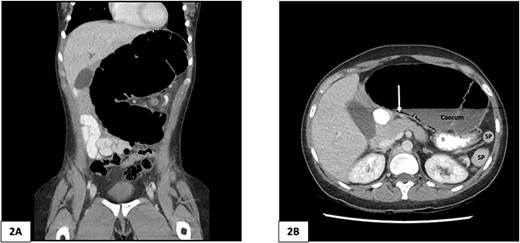

Computed tomography of the abdomen and pelvis of 25-year-old female patient. (A) Coronal slice demonstrating caecal volvulus with distended loop of colon. (B) Axial slice demonstrating 97 mm diameter distended caecum, multiple splenic fragments, arrow indicates pneumatosis coli, indicating colonic ischaemia. SP, spleen fragments.

A plain abdominal X-ray was performed showing a grossly distended loop of colon in the left upper abdomen. Subsequent computed tomography (CT) scan of the abdomen and pelvis was obtained using oral and intravenous contrast with images acquired during portal venous phase. The CT showed a mesenteric whirl sign (Fig. 1A) and caecal volvulus with the caecum measuring 97 mm diameter at its most distended point with associated pneumatosis coli (Fig. 2A and B).

There was malrotation of the gut with all colon on the left side and most of the small bowel on the right side of the abdomen (Fig. 2A). There was duplication of the infrarenal IVC, interruption of the suprarenal IVC with azygos continuation (Fig. 1C–F). A left-sided IVC draining venous blood from the left common iliac vein was present which drained into the left renal vein, while the right IVC drained blood from the right common iliac vein into the right renal vein. A retroaortic communication draining blood from the right IVC into the left IVC was also noted. From the renal veins all venous return was via the azygos vein to the superior vena cava with interruption of the suprarenal IVC. A suprahepatic IVC draining blood from the middle, left, and right hepatic veins into the right atrium was present (Fig. 1B). The spleen was divided into five distinct fragments, all within the splenic fossa and each supplied by an individual branch of the splenic artery (Figs 1 and 2).